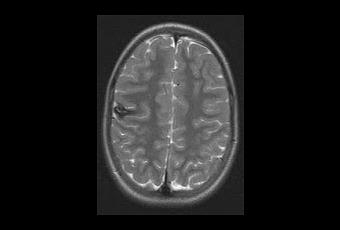

Los angiomas cavernosos (AC) son vasos

sanguíneos anormales localizados en el cerebro. Producen cefalea, trastornos

visuales, convulsiones y derrames cerebrales, tiene un componente genético,